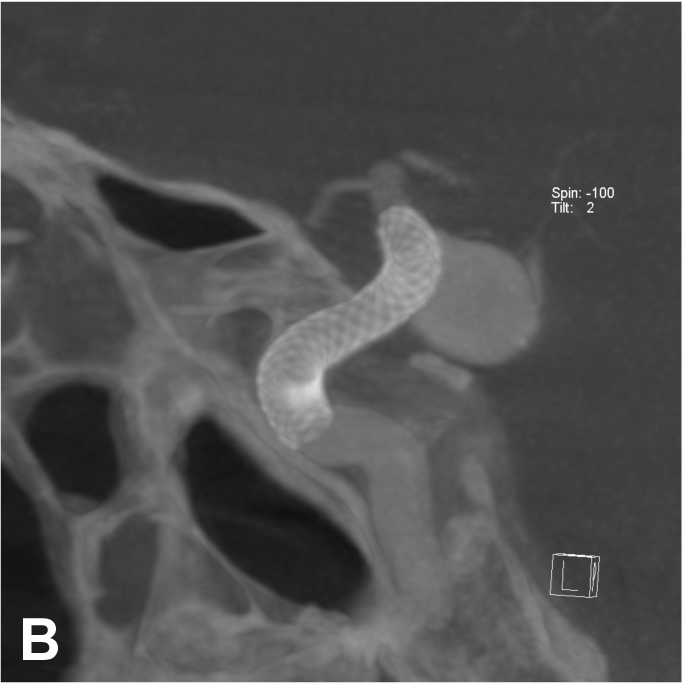

Exemple de traitement d’un anévrysme par stent « flow diverter ». A. Angiographie carotidienne de profil

mettant en évidence un anévrysme sacculaire. B. Acquisition type scanographique après positionnement

du stent dans l’artère porteuse. C. Contrôle à 1 an montrant une exclusion complète de l’anévrysme.